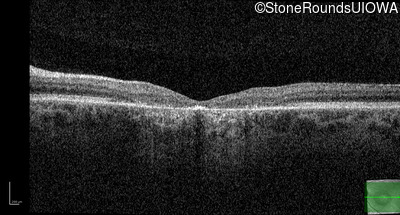

Age at visit: 17 years

OD OS

Age at visit: 17 years (Visit 2)

Age at visit: 21 years

Age at visit: 23 years

Age at visit: 25 years